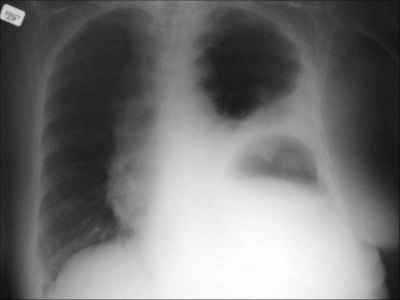

צילום בית החזה המבוצע כחלק מהערכת הפצוע הרב-מערכתי, יכול לספק מספר רמזים לגבי נוכחות קרע של הסרעפת: טשטוש גבולות הסרעפת, הרמת הסרעפת, בועות גז, או פלסי אוויר-נוזל, המצויים בצד בית החזה הפגוע, לחץ על הריאה בצד הנפגע עם הסטת המיצר לצד הנגדי (תצלום 19.16).